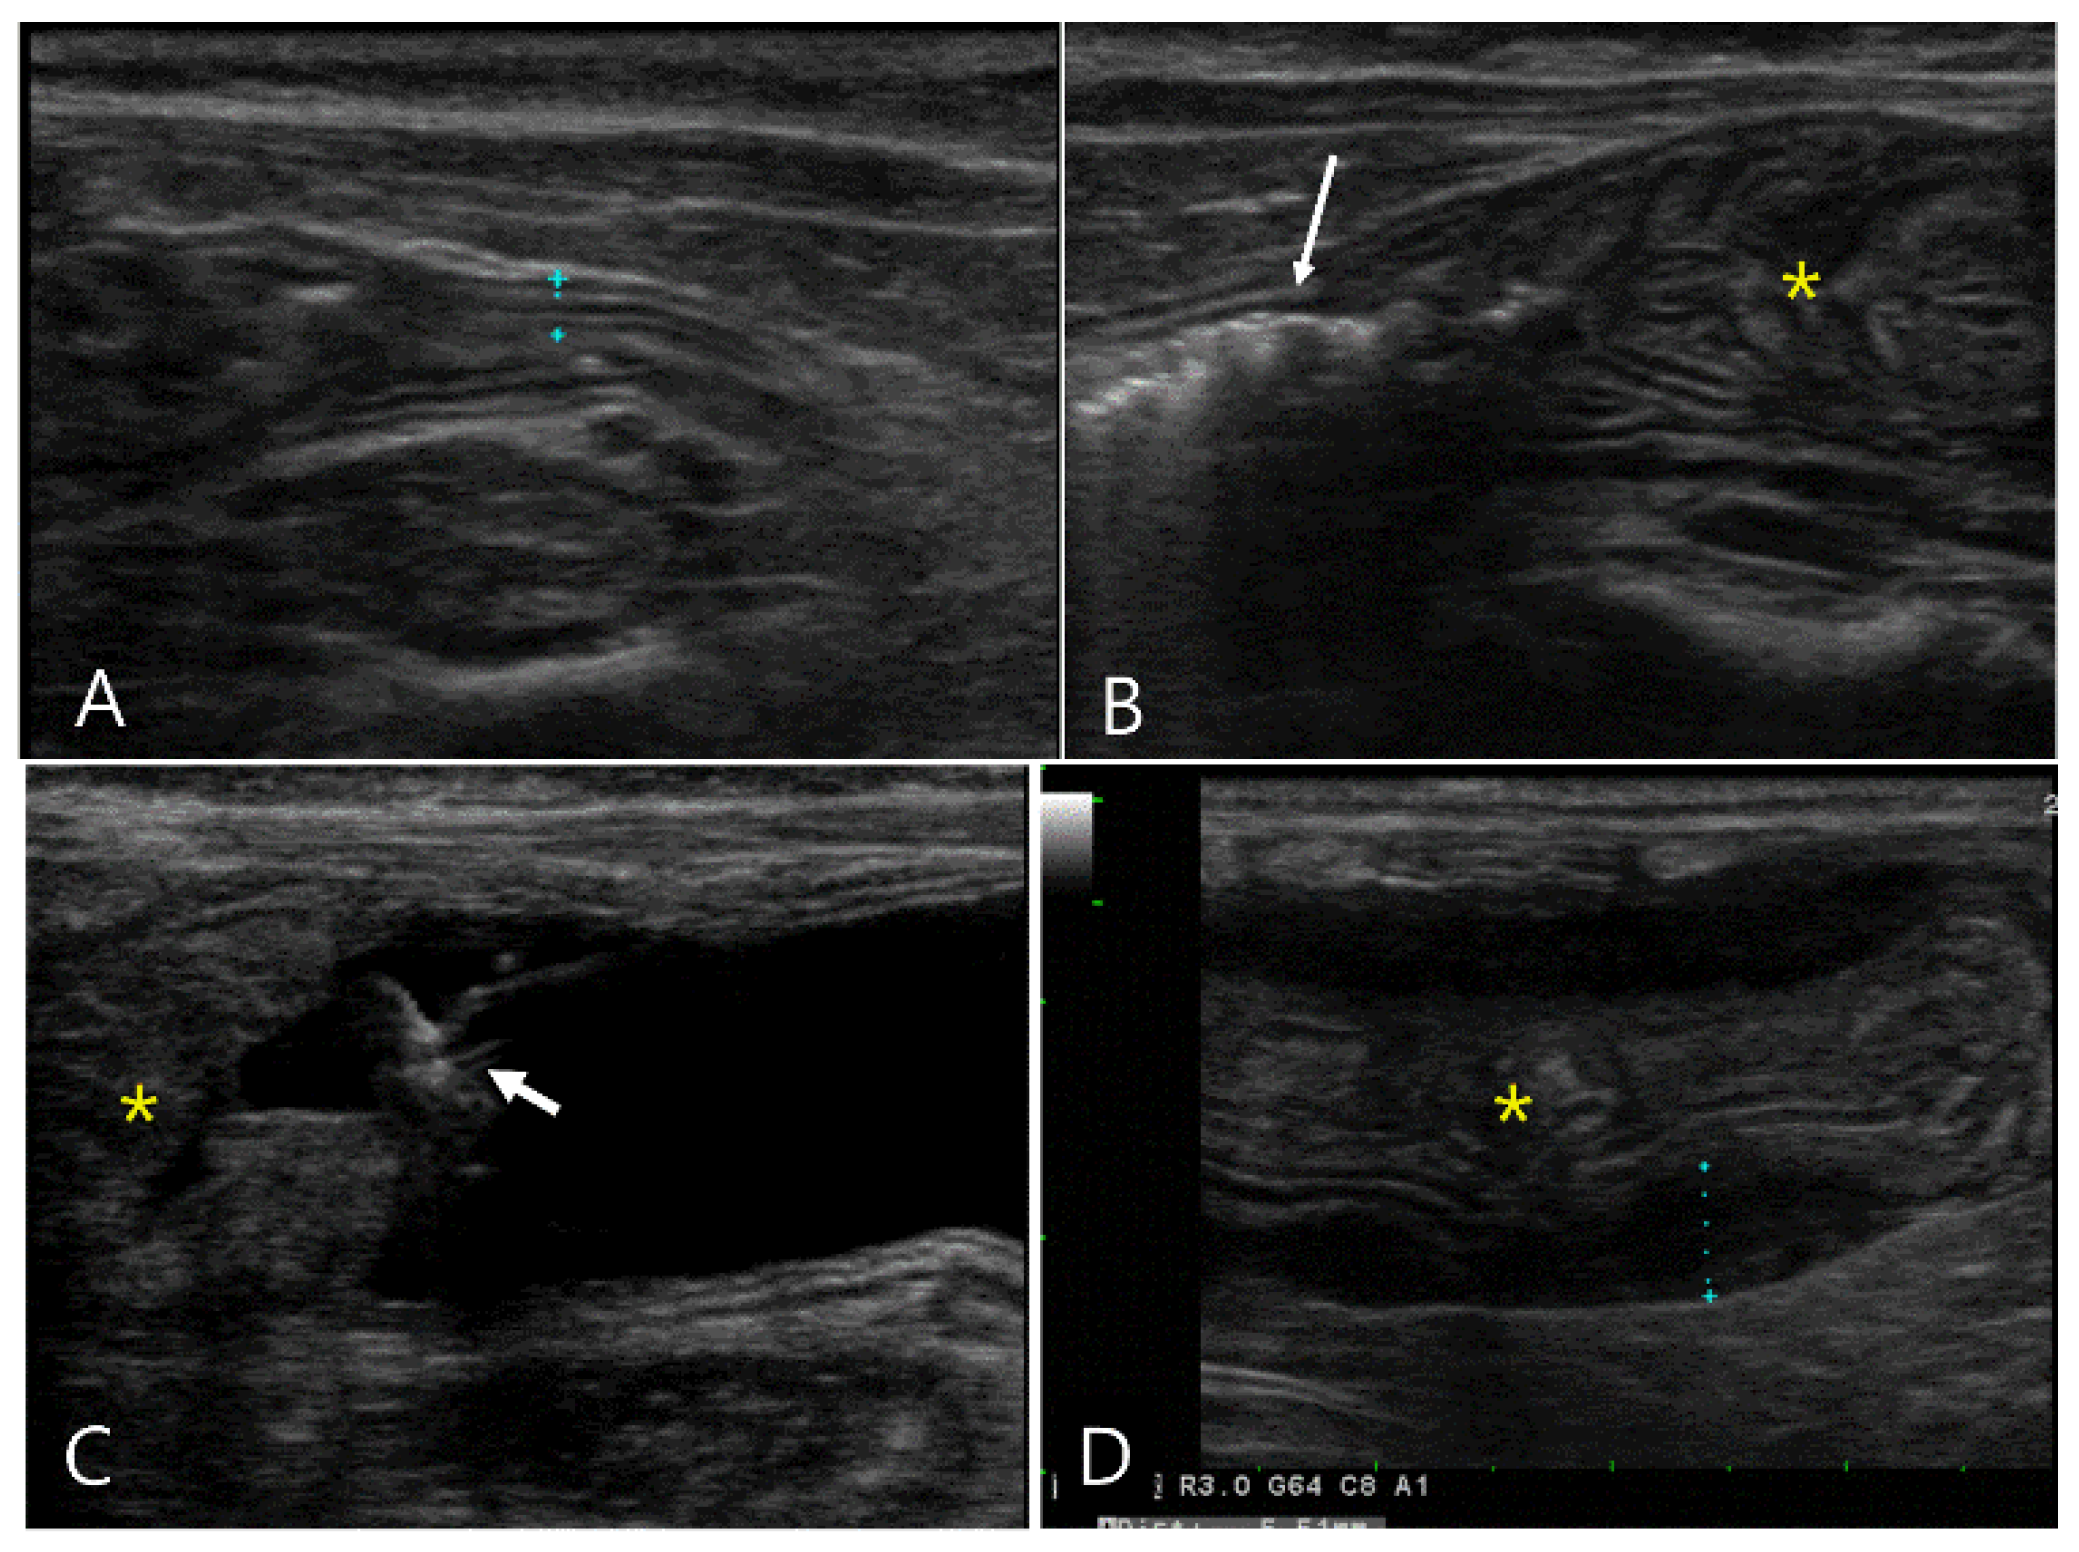

2.2. Case 2